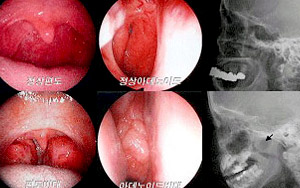

¸¸¼ºÆíµµ¼±¿°À̶õ?

Æíµµ´Â ¸ñÁ¥ÀÇ ¾çÂÊ¿¡ ÀÖ´Â ±¸°³Æíµµ¸¦ ¸»Çϳª, ½ÇÁ¦·Î´Â ±×°Í ¸»°íµµ ÄÚ µÚ¿¡ ÀÖÀ¸³ª ¸ñÁ¥ À§¿¡ ÀÖ¾î ´«À¸·Î´Â º¸ÀÌÁö ¾Ê´Â ¾Æµ¥³ëÀ̵å¶ó ºÒ¸®¿ì´Â ÀÎµÎÆíµµ ¹× Çô »Ñ¸®¿¡ ÀÖ´Â ¼³Æíµµ µîÀÌ ÀÖ½À´Ï´Ù.

ÀÌ·¯ÇÑ Æíµµ´Â Àӯı¸(¹éÇ÷±¸ÀÇ ÀÏÁ¾)µéÀÌ Ç³ºÎÇÏ°Ô ºÐÆ÷µÇ¾î ÀÖ´Â Á¶Á÷À¸·Î, Á¤»óÀûÀ¸·Î´Â ÀÌµé Æíµµ°¡ »ó±âµµ °¨¿°(°¨±â)¿¡ ´ëÇÑ ¹æ¾î ü°è¸¦ Çü¼ºÇϰí ÀÖÀ¸¸ç ¹Ýº¹ÀûÀÎ »ó±âµµ °¨¿°½Ã¿¡´Â ÀÌµé Æíµµ°¡ ºñÁ¤»óÀûÀ¸·Î ºñ´ëÇØÁ®¼ ¹®Á¦¸¦ ÀÏÀ¸Å°°Ô µË´Ï´Ù.

¢ÂÆíµµ¼±¿° ¹× Æíµµºñ´ëÀÇ Áõ»óÀº?

Æíµµ¼±¿°ÀÇ Áõ»óÀº ÀÚü°¡ °¨¿°¿øÀÌ µÇ¾î À¯¹ßÇÏ´Â Áõ»ó, Áï °í¿À» µ¿¹ÝÇÑ ¸ñ ºÎÀ§ÀÇ ÅëÁõÀÔ´Ï´Ù. ±Þ¼ºÀ¸·Î ¾Î°í Áö³ª°¥ ¼öµµ ÀÖÀ¸³ª ¸¸¼ºÈµÇ¸é ¹Ýº¹ÀûÀÎ ¿°¨±â¸¦ ÀÚÁÖ ¾ÍÀ½À¸·Î½á Àϳ⳻³» °¨±â¿¡ ½Ã´Þ¸®°Ô µÇ¸ç ¶ÇÇÑ Æíµµ°¡ ºñ´ëÇØÁ® Æíµµºñ´ëÁõ»óÀÌ ³ªÅ¸³ª°Ô µË´Ï´Ù.

±¸°³ÆíµµÀÇ ºñ´ë´Â ÄÚ°ñÀÌ, Ä¡¾ÆÀÇ ºÎÁ¤±³ÇÕ°ú °°Àº Áõ»óÀ» À¯¹ßÇÏ°Ô µÇ¸ç, ÄÚ µÚ¿¡ ÀÖ´Â ¾Æµ¥³ëÀ̵åÀÇ ºñ´ë´Â ÄÚ¸·Èû, ±¸°È£Èí, ÄÚ°ñÀÌ, ¼ö¸é½Ã ¹«È£Èí, »ïÃ⼺ ÁßÀÌ¿° º´¹ß µîÀÇ ½É°¢ÇÑ Áõ»óÀ» À¯¹ßÇÕ´Ï´Ù.